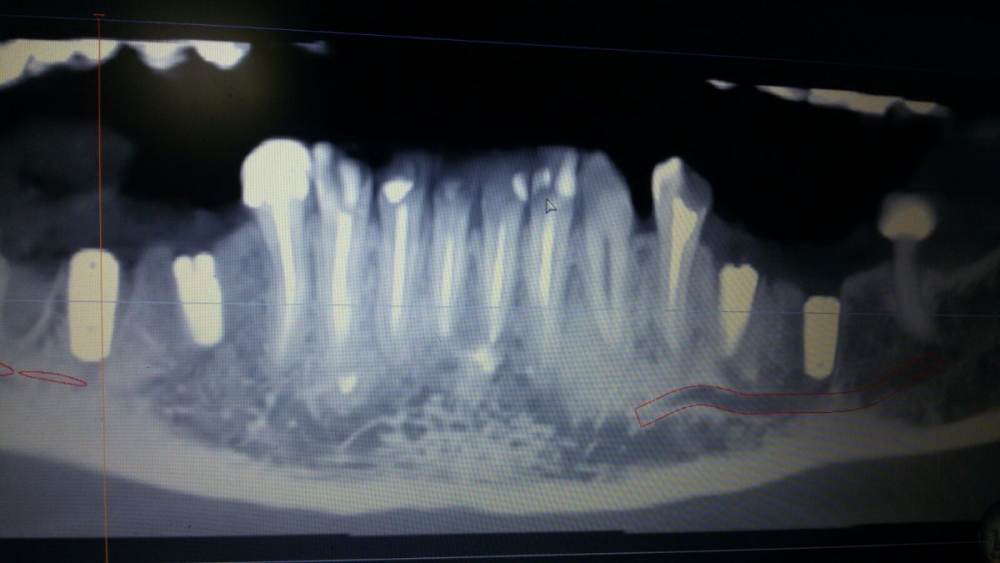

chealena Опубликовано 14 августа, 2021 Поделиться Опубликовано 14 августа, 2021 Здравствуйте ! В среду мне установили 4 импланта по две на каждые стороны нижние, слева также удаляли зуб и туда сразу ставили имплант. После этого у меня сейчас онемевшая губа и часть зубов и часть подбородка, что мне делать? Врач говорит что все нормально и нерв не был задет, а я вижу что на кт снимке идёт траншея до нерва , как будто он просверлил туда. Говорит мне ничего не делать и просто ждать. Но онемение не проходит, уже и отёк спал , а онемение есть и это ужасно противно, и когда пальцем вожу по этому месту очень неприятно как будто песок. Зуб слева первый имплант на снимке. Подскажите пожалуйста что делать! Ссылка на комментарий

Irouil Опубликовано 14 августа, 2021 Поделиться Опубликовано 14 августа, 2021 Как и что могло случится - это спрашивать стоит только у того человека, который видел своими глазами что и как случалось. Иначе говоря, эти вопросы надо задавать лечащему врачу. Выкручивание имплантов, судя по предоставленным снимкам, никак не повлияет на ситуацию с онемением. Но это не отменяет Вашей симптоматики, а значит какое-то влияние на нерв есть. Неврологическая терапия поможет снизить это влияние и ускорить процесс восстановления чувствительности. Ссылка на комментарий

Irouil Опубликовано 16 августа, 2021 Поделиться Опубликовано 16 августа, 2021 15.08.2021 в 00:45, chealena сказал: Но если нерв не поврежден почему у меня пол губы немые вместе с подбородком и частью зубов? Воздействия на нерв не ограничиваются только его повреждениями. Даже отёк от проведённой операции способен создать иногда достаточную компрессию чтобы вызвать транзиторную парестезию. Импланты в канал не пенетрируют, это самое главное. Руками хирурга тут особо нечего изменить/исправить. Применение физиотерапевтических процедур может ускорить реабилитацию. 2 Ссылка на комментарий